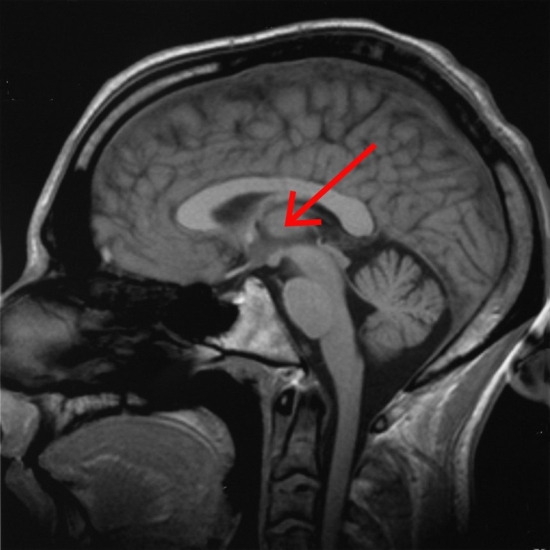

A befutó információk szabályos elrendezése a CGL-ben a vizuális feldolgozásnak azokat a további fázisait segíti, amelyek az elsődleges látókéregben, a V1-ben zajlanak le. A fenti kép ezt foglalja össze. A tárgyról a szem optikája képet formál, mely a szem hátsó falán lévő retinára vetül. A látóideg, mely a retinális ganglionsejtek kivezető huzaljait (axonok) tartalmazza, egy agykéreg előtti idegmagba juttatja a kivonatolt információt. Ebből a magból (CGL) azután egy átkapcsolással az agykéreg elsődleges látókérgébe (V1) vetül a látópálya.